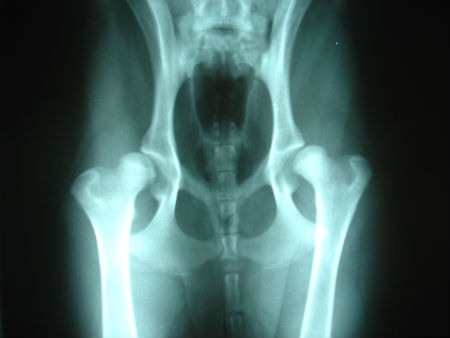

Aunque existen enfermedades que se pueden prevenir según la calidad de vida de nuestra mascota, hay una cantidad de patologías que aparecen por factores difíciles de controlar, como por ejemplo, la genética. Una de las más mencionadas en este caso es la displasia de cadera. Una condición muy común en perros de diferentes razas que puede afectar la movilidad del canino, hasta el punto de limitar completamente su andar, debido al dolor que progresivamente se va agudizando. Pero ¿qué es?, ¿cómo identificarla?, ¿qué debemos hacer ante esta enfermedad? Todos estos interrogantes son frecuentes, pues si bien es muy común en los perros, existen dueños que aún no la conocen. Por esta razón, hemos desarrollado un artículo dedicado en profundizar a la displasia de cadera. No dejes de leerlo, te ayudará a conocer en detalle cada aspecto de esta afección. ¿Qué es? Al igual que el cuerpo humano, el sistema óseo de los perros se encuentra unido por una especie de «engranajes», lo que permite el funcionamiento y movilidad de cada articulación. Si estos engranajes no encajan a la perfección en alguna de sus cavidades, puede presentarse una alteración en el canino, entre las más comunes se encuentra la displasia de cadera y la displasia de codo. Este tipo se trata de una malformación en el área de la cadera, también conocida como zona coxofemoral, la cual se presenta cuando la cabeza del fémur (cuya forma es una bola) no encaja debidamente en la cavidad cóncava que le corresponde (denominada acetábulo) y que se encuentra dentro del hueso pélvico. Este desajuste produce que el desarrollo de la articulación no se lleve a cabo de forma adecuada. Esto sucede dado que la cabeza del fémur, al no estar recubierta, no permanece en la mencionada cavidad, sino que, por el contrario, se mueve desordenadamente, lo que a la larga produce debilidad de los tejidos musculoesqueléticos del perro, acompañada de dolor e inflamación. Hablamos de una enfermedad degenerativa. Es decir, que no se envidencia claramente en las primeras semanas de vida del canino, sino que se va notando con su crecimiento y desarrollo, pues el desgaste de los tejidos con el movimiento inadecuado de la cabeza del fémur, hace más visible la patología progresivamente. Por lo que será hasta los cuatro o seis meses, y en algunos casos en la edad adulta, cuando se empiecen a notar indicios de esta enfermedad. ¿Cuáles son las razas más afectadas por la displasia de cadera? Esta patología afecta con mayor frecuencia a perros grandes y de gran peso, aún más cuando no han recibido cuidados adecuados como el suministro necesario de calcio, una alimentación equilibrada y una rutina de ejercicios favorable para reforzar sus articulaciones. No obstante, en ciertos casos, esta enfermedad puede aparecer en perros de razas pequeñas, pero con menos incidencia que en los señalados. A continuación, veamos algunas de las razas más propensas a ser afectadas por la displasia de cadera: Pastor alemán Pastor Belga San Bernardo Gran danés Mastín del Pirineo Mastín napolitano Bulldog francés Bulldog inglés Estas razas son las más asociadas a la enfermedad, debido no solo a su tamaño y peso, sino también a otros factores que les hacen más propensos a padecerla. El conocimiento acerca de la raza y de cómo prevenir o disminuir los factores de riesgo asociados a esta condición puede ayudar a brindar a nuestras mascotas los cuidados adecuados para su bienestar. Causas La displasia de cadera puede verse como una enfermedad multicausal, debido a que cuenta con diferentes factores de riesgo (tanto biológicos como ambientales) que pueden incrementar la posibilidad de su aparición. Veamos a continuación los factores de riesgo asociados a ella: Ambientales Dentro de los factores ambientales, se pueden ubicar aspectos relacionados con la calidad de vida que las personas ofrezcan a sus mascotas, debido a que, si el perro recibe los cuidados necesarios, disminuirá la posibilidad de padecer esta afección. Podemos mencionar como factores ambientales los siguientes: Mala alimentación Sin duda alguna la alimentación inadecuada es uno de los factores más relacionados a la displasia de cadera. Acompañado a una deficiencia de calcio y minerales en la dieta canina. Que un perro no reciba una adecuada nutrición puede también desencadenar obesidad, aspecto que influye notoriamente en la aparición de la enfermedad. Sendentarismo Aunque parezca insignificante, la práctica de ejercicios en la vida de un perro es esencial. Aún más si se trata de razas grandes y de mucho peso, pues esto le ayudará a mantenerse en forma y evitar aspectos tan importantes como la obesidad. El sedentarismo para el canino puede ser realmente perjudicial, pues además de ganar peso, puede atrofiar sus articulaciones e incrementar las posibilidades de que aparezca la displasia. Biológicos El factor considerado el causante más crítico dentro de la displasia de cadera es el hereditario. En estos casos, está relacionada de forma más frecuente con perros grandes y pesados como los de la lista anterior. Sin embargo, en caninos de menor peso y talla, como Spaniel o Pug, es normal que aparezca esta enfermedad en algunas ocasiones. De cualquier forma, aunque el factor genético siempre sea una constante y difícil de prevenir, los factores ambientales suelen ser controlables en gran medida y permitirán que el perro goce de buena calidad de vida y salud, si se le dan los cuidados adecuados. Síntomas de la displasia de cadera Debido a que se trata de una enfermedad progresiva y degenerativa, los síntomas no aparecen de una sola vez, sino que se van agudizando conforme el perro crece. Siendo también intermitentes, es decir, que posiblemente no siempre estarán presentes. Veamos qué manifestaciones pueden presentar los caninos con esta enfermedad: Rechazo a realizar actividades físicas como subir escaleras Tendencia a la inactividad Dolor progresivamente agudo Dificultad para desplazarse Cojera Rigidez en la parte trasera Inestabilidad Tristeza Apatía a jugar o correr Espalda curvada Limitación para levantarse Aumento de los músculos delanteros Estos son los síntomas más frecuentes de la displasia de cadera en perros. A medida que va avanzando la enfermedad, factores como el dolor pueden aumentar, al igual que la dificultad para desplazarse, hasta el punto de que el perro puede perder totalmente la movilidad debido a las molestias que esto le ocasiona. Tratamientos Propiamente, esta es una enfermedad que no tiene cura. Sin embargo, pueden aplicarse en el perro una especie de tratamientos que le ayuden a mejorar su calidad de vida, a minimizar los episodios de dolor y a sentirse un poco más aliviado. Estos tratamientos pueden ser quirúrgicos o no quirúrgicos, ambos dependerán en gran medida del avance de la enfermedad. Considerando también otros factores, desde el tamaño y edad del perro, hasta el coste que pueda tener el tratamiento. A continuación exponemos en qué consisten cada uno de estos tratamientos: Quirúrgicos La cirugía para intentar corregir la displasia de cadera se define como triple osteotomía pélvica. En este caso, la cabeza del fémur es enlazada a la cavidad correspondiente de manera artificial mediante placas que le ayudan a mantenerse en su lugar. Esta cirugía se realiza, en la mayoría de los casos, cuando el tratamiento no quirúrgico ya no hace el mismo efecto. No obstante, presenta grandes riesgos, por lo que es necesario contar con la orientación del veterinario en todo momento para decidir si debemos realizarla o no. No quirúrgicos El tratamiento médico no quirúrgico está más inclinado a la administración de medicinas que ayuden al perro a aliviar el dolor y la incomodidad causada por la enfermedad. Antiinflamatorios y analgésicos son los que en mayor medida se suministran para este fin. Por otro lado, estos se complementan con sesiones de hidroterapia y fisioterapia que contribuyen a fortalecer los músculos y aliviar el dolor. Los tratamientos no quirúrgicos son aplicados cuando la displasia se encuentra en su fase más leve. De esta manera se desacelera su progresión aunque no se detenga. Aunque la displasia de cadera se trata de una enfermedad no curable y difícil de prevenir por su factor genético, existe la posibilidad de ofrecer a nuestras mascotas una buena calidad de vida, atención y cuidados que le mantengan saludable y alejen en la medida de lo posible esta condición. Otros artículos sobre salud canina que te pueden interesar: Tos de las perreras Anemia canina Plantas tóxicas para perros Cómo tratar el resfriado de mi perro Alergia alimentaria en perros Caspa en perros